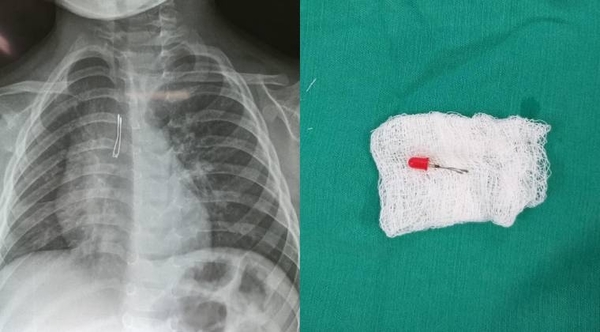

HOY / Niño de 2 años ingirió foquito de su juguete y debió ser llevado al quirófano

Un niño de tan solo 2 años tragó accidentalmente el foco de uno de sus juguetes, ocasionándole problemas respiratorios que derivaron en una ...[Leer más]